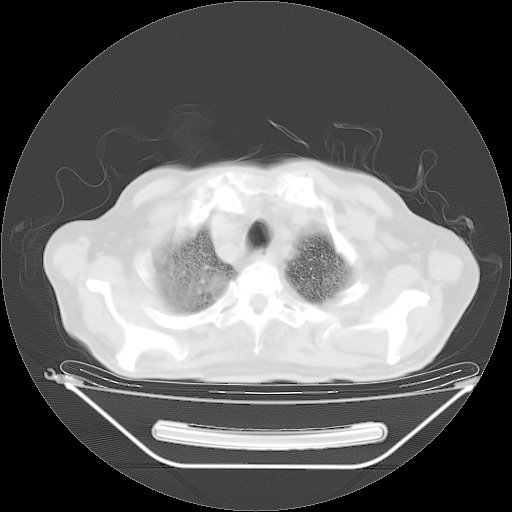

今天复查肺部CT,发现双肺广泛磨玻璃样改变。所以我把3月19日和5月9日相隔50天的肺部CT上传。请大家会诊。

5月9日肺部CT(在4月27日齐鲁医院肺部CT描述部分肺组织磨玻璃样改变,12天后肺组织广泛磨玻璃样改变)

2009年5月9日肺部CT

大致读了系列胸部CT:纵隔窗无明显异常,肺窗:从4、27至今:主要是双肺中下野外带可见毛玻璃样改变,目前处于急性肺泡炎阶段,至于原因考虑1、结替组织或胶原血管性疾病所致?2、恶性疾病如恶组在肺部所致的表现或细支气管肺泡癌?3、药物或其它原因如肺蛋白沉着症所致肺泡炎目前不太可能?总之,明天就去请我院的呼吸科、感染科、血液科和临免专家会诊哈。